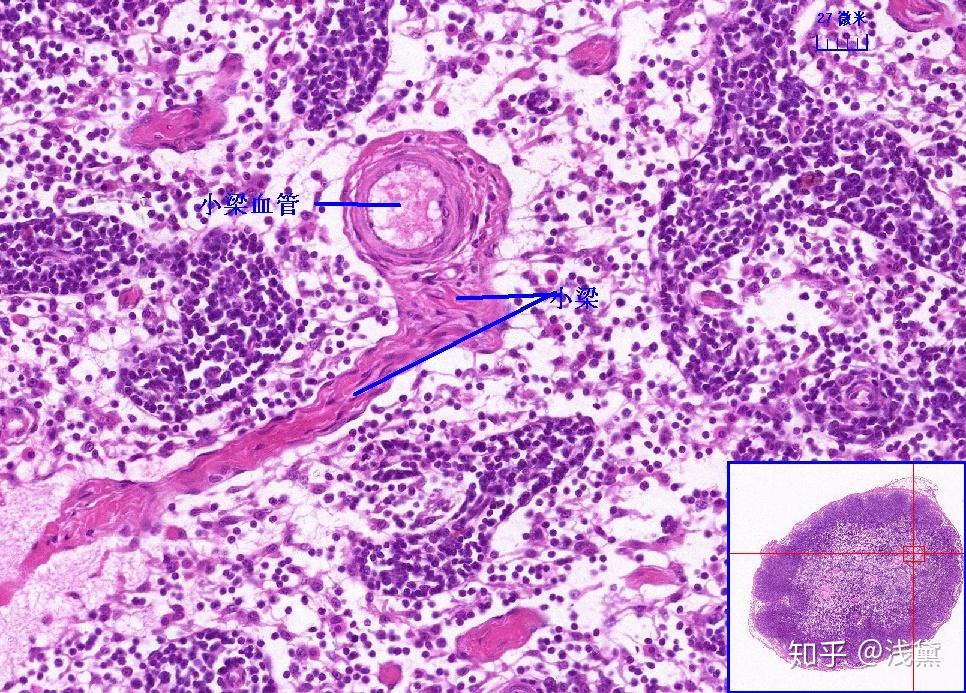

胸腺小体(きょうせんしょうたい、英:Hassall's body)とは胸腺髄質において胸腺細網細胞(胸腺上皮細胞)が同心円状に配列した領域。ハッサル小体とも呼ばれる。胸腺小体は30~100μm程度の大きさであり、中心には1個あるいは数個の変性度の高い大型細胞が位置する。